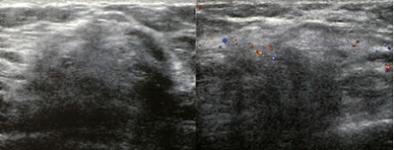

👉In addition to MRI and molecular imaging, both tomosynthesis and breast ultrasound are additional techniques for enhanced screening in patients with dense breasts.

👉A prospective multicenter study compared tomosynthesis with bilateral physician hand-held ultrasound screening in 3231 asymptomatic patients with mammography-negative dense breasts.

– In all, 24 additional cancers were detected, 23 of which were invasive.

– Tomosynthesis detected 13 cancers, and ultrasound detected 23.

– These data suggest that even though tomosysthesis significantly increases the number of cancers found in dense breasts, in the hands of a skilled breast radiologist, ultrasound may be even better.